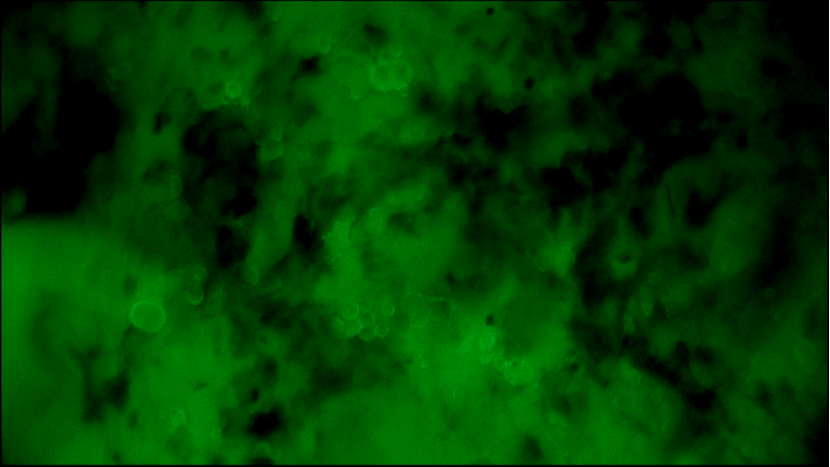

術(shù)中EndoSCell?細(xì)胞圖像如下:

左乳腫物:部分區(qū)域細(xì)胞核密集,分布不均,形態(tài)異常。